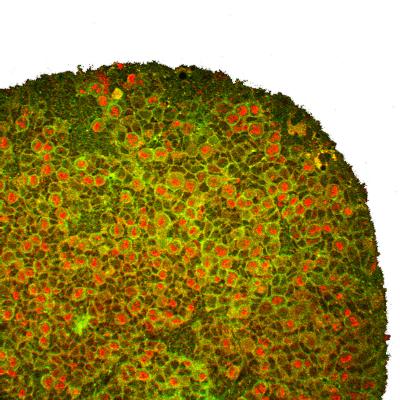

Using fluorescent staining and laser-scanning microscopy, the eight-member research team studied various mutations in a gene called aurora-A to observe how changes in protein expression affected the ability of Drosophila neuroblasts, a type of neural stem cell, to maintain their stem cell character without forming tumors.

In Drosophila, Doe's team found that a mutation in aurora-A, an evolutionary conserved gene in fruit flies and humans, results in two distinguishing problems: Proteins (Numb) involved in the differentiation into neurons and neuroblast self-renewal (aPKC) are not sorted to their proper sides of the cell, and the mitotic spindle that provides cortical polarity becomes misaligned. The subsequent splitting leads to new cells with improper proteins mixes, including an overproduction -- in this case 10 times more than normal -- of new neuroblasts that lead to tumors in the brain.